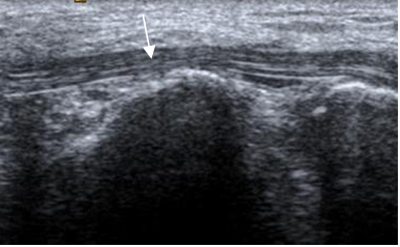

Fig 19. Fascia plantar normal.

A y B: RM axial en T1 y C: RM coronal en T1. Rama medial (Flecha delgada), central (Flecha gruesa) y lateral (Cabeza flecha).

Fig 20. Fascia plantar normal.

A: RM sagital en T2 y B: RM sagital en STIR. Estructura hipointensa en todas las secuencias.

Fig 21. Fascia plantar normal en ecografía, corte sagital.